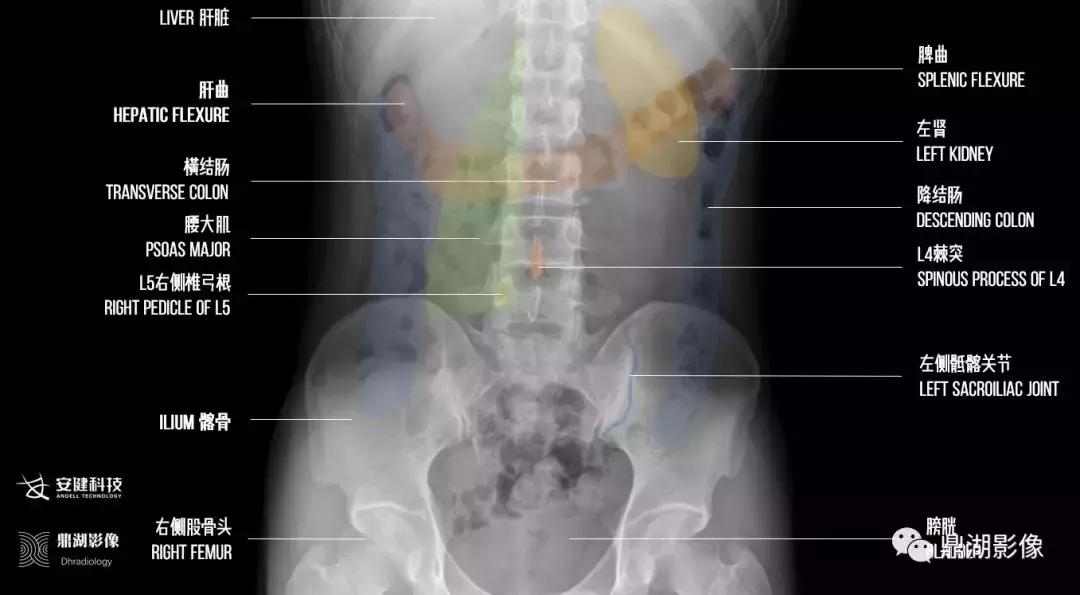

以上图像由安健科技提供

鼎湖影像标注

由上图标注可以看出腹部平片左边的图像是被检者的右侧,右边的图像是被检者的左侧。这个是基础知识。